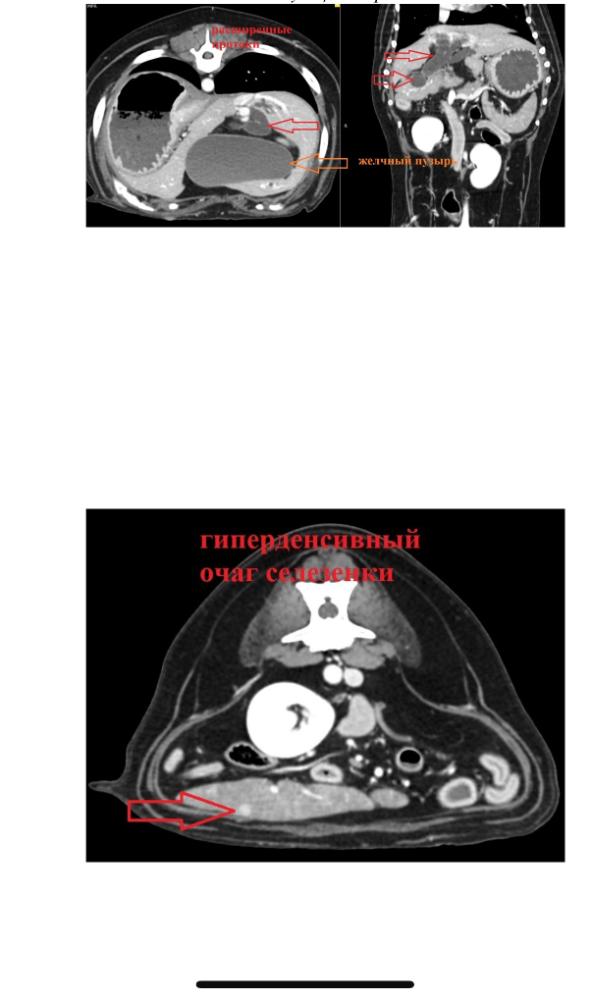

Mosfilmka & Remy Опубликовано 24 февраля, 2023 Опубликовано 24 февраля, 2023 Дорогие форумчане, Лялечке очень срочно нужна наша помощь!!! 🆘 Девочке 11 лет, каждые полгода ребенок обследуется, принимает нужные лекарства по состоянию здоровья. С 2020 года Ляля пьет Урсофальк и Гептрал курсами. У нее сильный загиб желчного, и поэтому надо поддерживать. Спасибо огромное пенсионной группе за поддержку!! Вчера утром девочку вырвало. Сегодня Ляля поехала на УЗИ и сдавать кровь, и по заключению и анализам Алексеева сказала ехать на КТ и в итоге обязательно сдаваться на операцию по удалению желчного пузыря. Елена Анатольевна сказала, что этот вопрос не требует отлагательств, дело срочное, надо разбираться и решать! Это большие суммы - КТ 14000, проверка сердца под ключ - около 12000, а вилка по операции 30-50000руб. Итого по расходам на днях до 80000руб! 🤯 Лялечка живет в семье, любима, в заботе, там живет еще одна кураторская собака, благодарны за то, как они смотрят и ухаживают за ними! 🙏 Светлана, куратор, все эти годы за свой счет всегда обследует Лялю и приобретает препараты, пенсии хватает только на еду. К сожалению, у нас сейчас СОВСЕМ нет финансов. А у кураторских собак резко за эти два дня начали обостряться проблемы по здоровью!! Мы очень просим помощи и поддержки!! Ляля записана к кардиологу на завтра, а в воскресенье на КТ. Вчера на обследование уже ушло 10800руб. Что делать, куда бежать, откуда взять такие суммы за сутки-двое – неясно 😭 РЕБЯТА, ПОМОГИТЕ, ПОЖАЛУЙСТА!! ОЧЕНЬ ПРОСИМ ПОМОЩИ!! Баланс на 2020: минус 11.731 , 50 коп Пополнение: 2000руб Наталья Авеглант ИТОГО БАЛАНС 2020: минус 9731руб Расход 2023: 10800руб анализы, чистка желез, УЗИ ИТОГО БАЛАНС: МИНУС 20531руб Карта Сбербанк 4279 3800 1813 3431 Светлана У Карта Тинькофф 5536 9137 9790 0954 Светлана У В комментариях очень просим писать "Ляля" и обязательно отписываться здесь, в теме.❤️ Спасибо!

Mosfilmka & Remy Опубликовано 24 февраля, 2023 Опубликовано 24 февраля, 2023 Анализы говорят сами за себя, что состояние очень острое и нехорошее 😭 1

Mosfilmka & Remy Опубликовано 24 февраля, 2023 Опубликовано 24 февраля, 2023 А вот июльские исследования, такого ужаса не было 😔 1

Mosfilmka & Remy Опубликовано 25 февраля, 2023 Опубликовано 25 февраля, 2023 Сегодня прием кардиолога, пред операционная проверка сердца, завтра КТ. Потом запись на удаление желчного! Помогите оплатить все это, пожалуйста! Лялечка очень нуждается в поддержке! Мы со Светой уже так закредитнулись, что банки нам отказывают (((